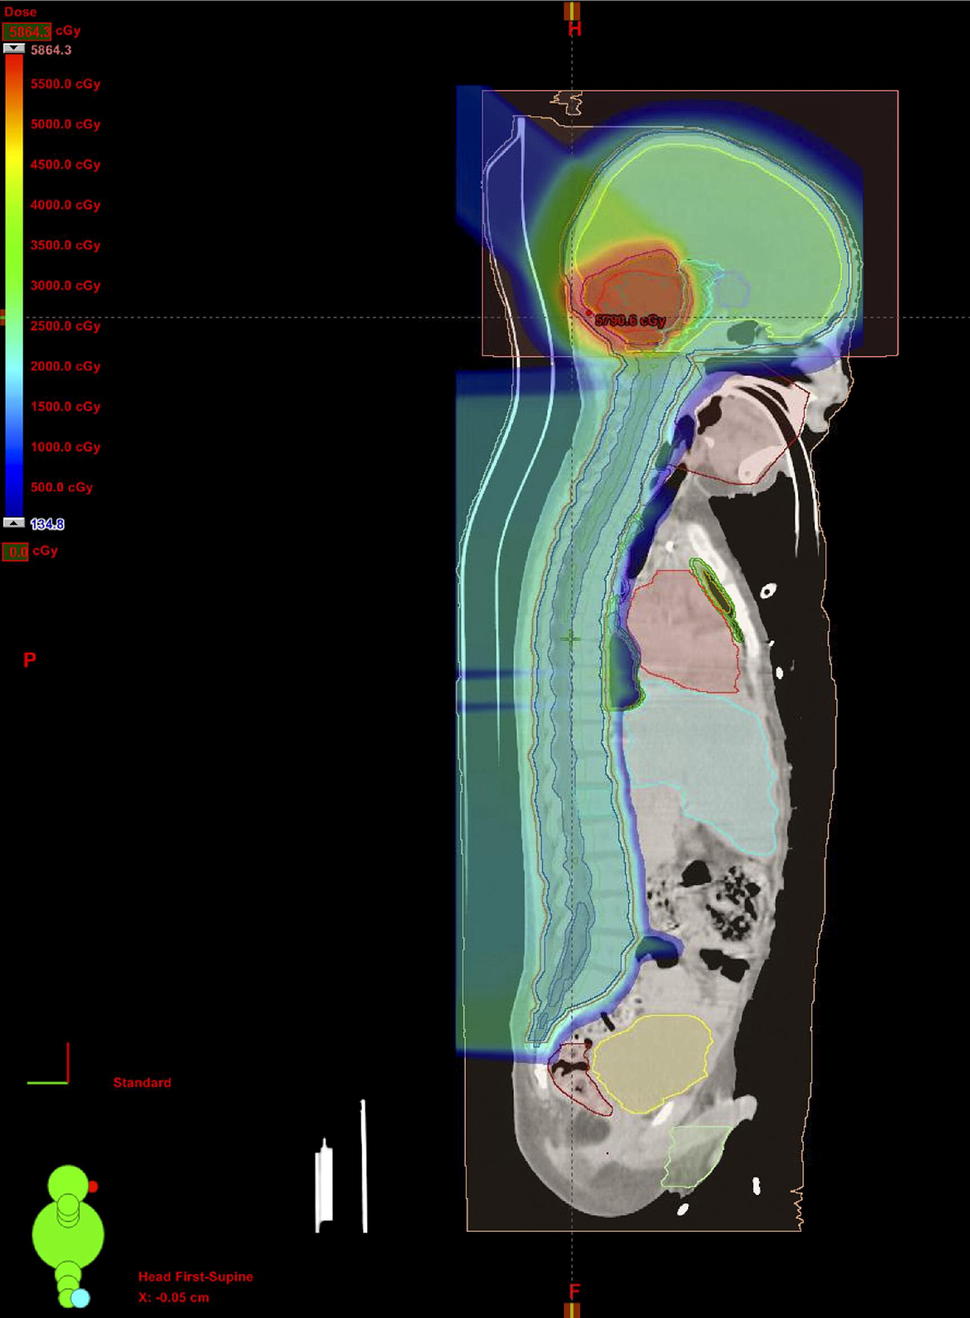

Children with average-risk medulloblastoma typically have surgery to remove as much of the tumor as possible, followed by chemotherapy plus several weeks of radiation. That includes radiation to the whole brain and spine, as well as an extra “boost” to the cerebellum and brain stem, where medulloblastoma tumors start growing.

All trial participants received either the standard radiation boost to the base of the skull, or a boost to a smaller area of the brain. The smaller the area, the less healthy tissue that will be hit with radiation, Dr. Buchsbaum explained. That can potentially spare areas of the brain involved in hearing, memory, and hormone regulation, he added.